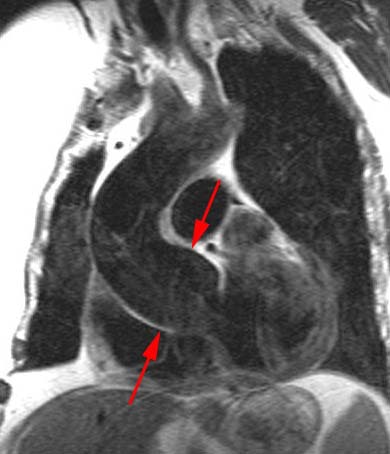

Marfan's Syndrome:

In the images below, the arrows point to the dilated aortic root which has a characteristic "onion bulb" or "pear" shape. The sinotubular junction is effaced, and there is mild aneurysmal enlargement of the sinuses of Valsalva (measuring 5.1 cm).